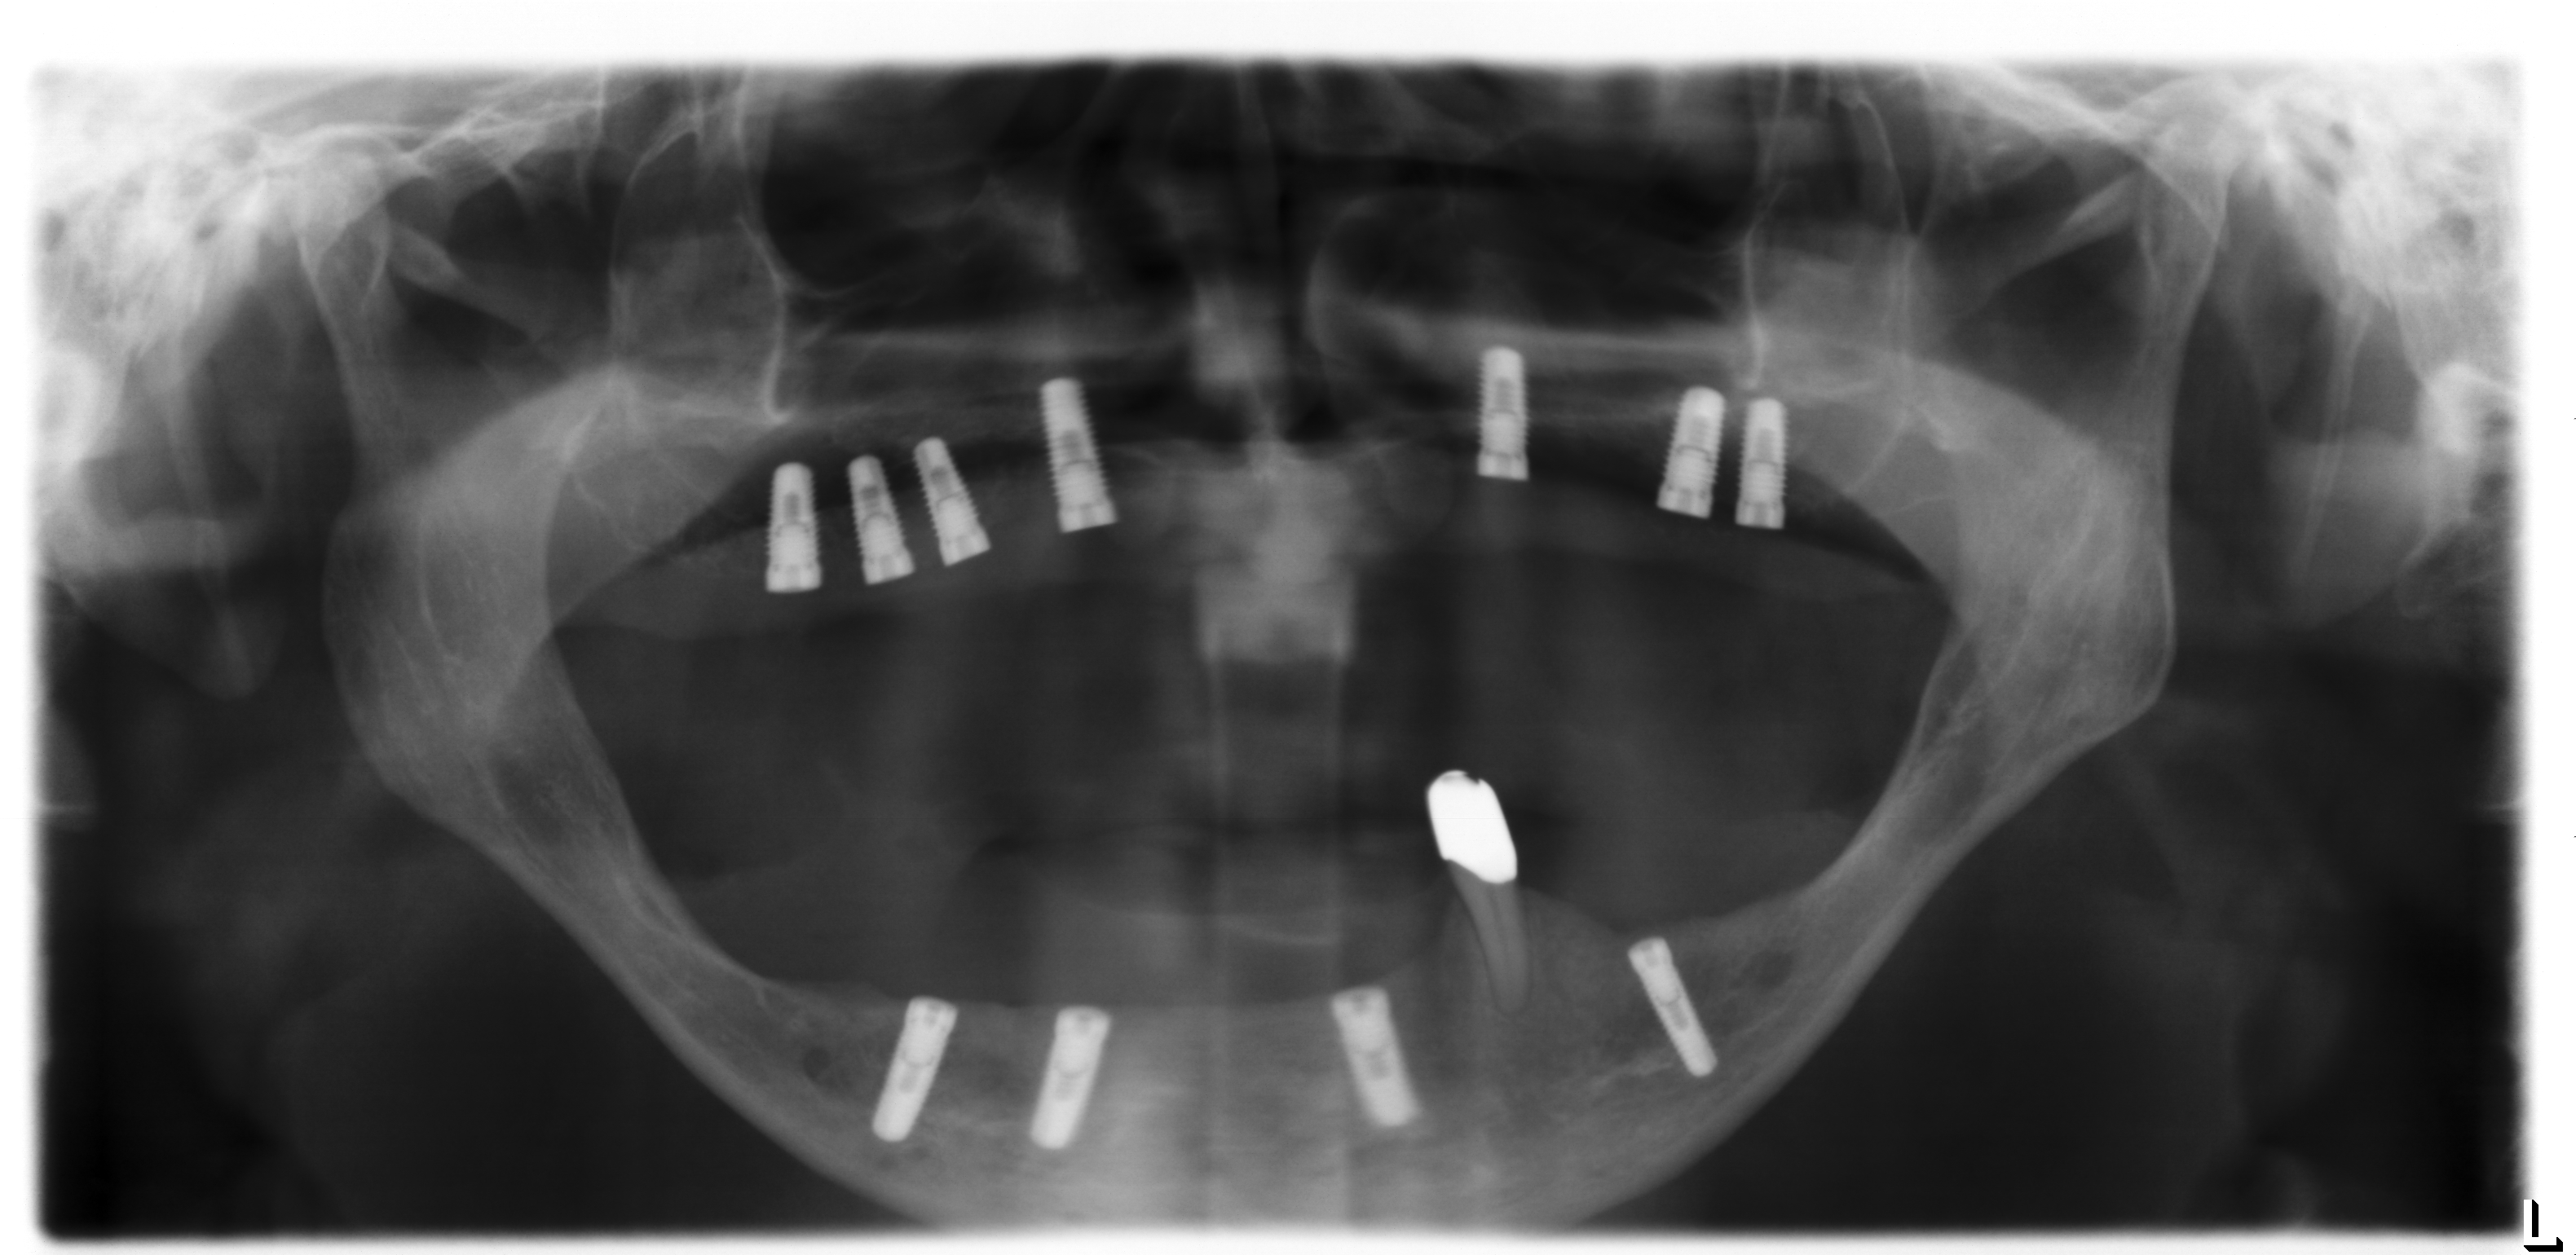

Für derart komplexe Fälle ist das interdisziplinäre Zentrum für Zahnärztliche Implantologie der Ansprechpartner: Der Patient wird in einer interdisziplinären Sprechstunde vorgestellt und die Planung des Patienten in dem interdisziplinär geleiteten Implanatboard erstellt. Anschließend erfolgt der Knochenaufbau in ITN. Dabei werden die angelagerten Knochenstücke über sogenannte Osteosyntheseplatten in den Bereichen fixiert, an denen später die Implantate gesetzt werden sollen (Abb.6). Zeitgleich erfolgte im Unterkieferbereich eine Nervverlagerung des Unterkiefernervs und im Oberkiefer eine Knochenaufbau im Bereich der Kieferhöhlen (sogenannter „Sinuslift“) (Abb.7). Nur durch diese ausgedehnten Augmentationsmaßnahmen ist ein späteres Einbringen der Implantate sinnvoll möglich. Vier Monate später erfolgt die Entfernung der Osteosyntheseplatten (Abb.8) in Kombination mit dem Setzen der Implantate (Abb.9). Die genaue Position der Implantate wird dabei über eine individuell hergestellte Schablone (sogenannte Bohrschablone) festgelegt (Abb.10).

Damit stellt man sicher, dass die Implantate hinterher auch an der richtigen Position stehen und den späteren Zahnersatz optimal unterstützen (Abb.11). Abschließend erfolgt die prothetische Versorgung des Patienten. Dazu werden die Implantate im Mund abgeformt (Abb.12) und mit Hilfe einer „Abformung“ auf ein Gipsmodell übertragen (Abb.13). Auf diesem wird anschließend die prothetische Versorgung hergestellt (Abb.14). In diesem speziellen Fall wurde für den Oberkiefer eine steggetragene Prothese (Abb.15, Abb.16) hergestellt. Dieser wird dann auf den Implantaten im Mund verschraubt (Abb.15) und darüber eine herausnehmbare Prothese (Abb.17) verankert (Abb.16).

Diese sehr aufwändigen prothetischen Arbeiten sind starr mit den Implantaten verbunden, so dass der Patient wieder das Gefühl von „echten und feste Zähne“ hat (Abb.21, Abb.22). Dennoch sind sie zur Reinigung der Implantate durch den Patienten herausnehmbar. Abbildung 23 zeigt die mit Steg bzw. Teleskopen versorgten Implantate. Details zur den Verankerungen der Prothesen (siehe Abb.24, Abb.25, Abb.26).